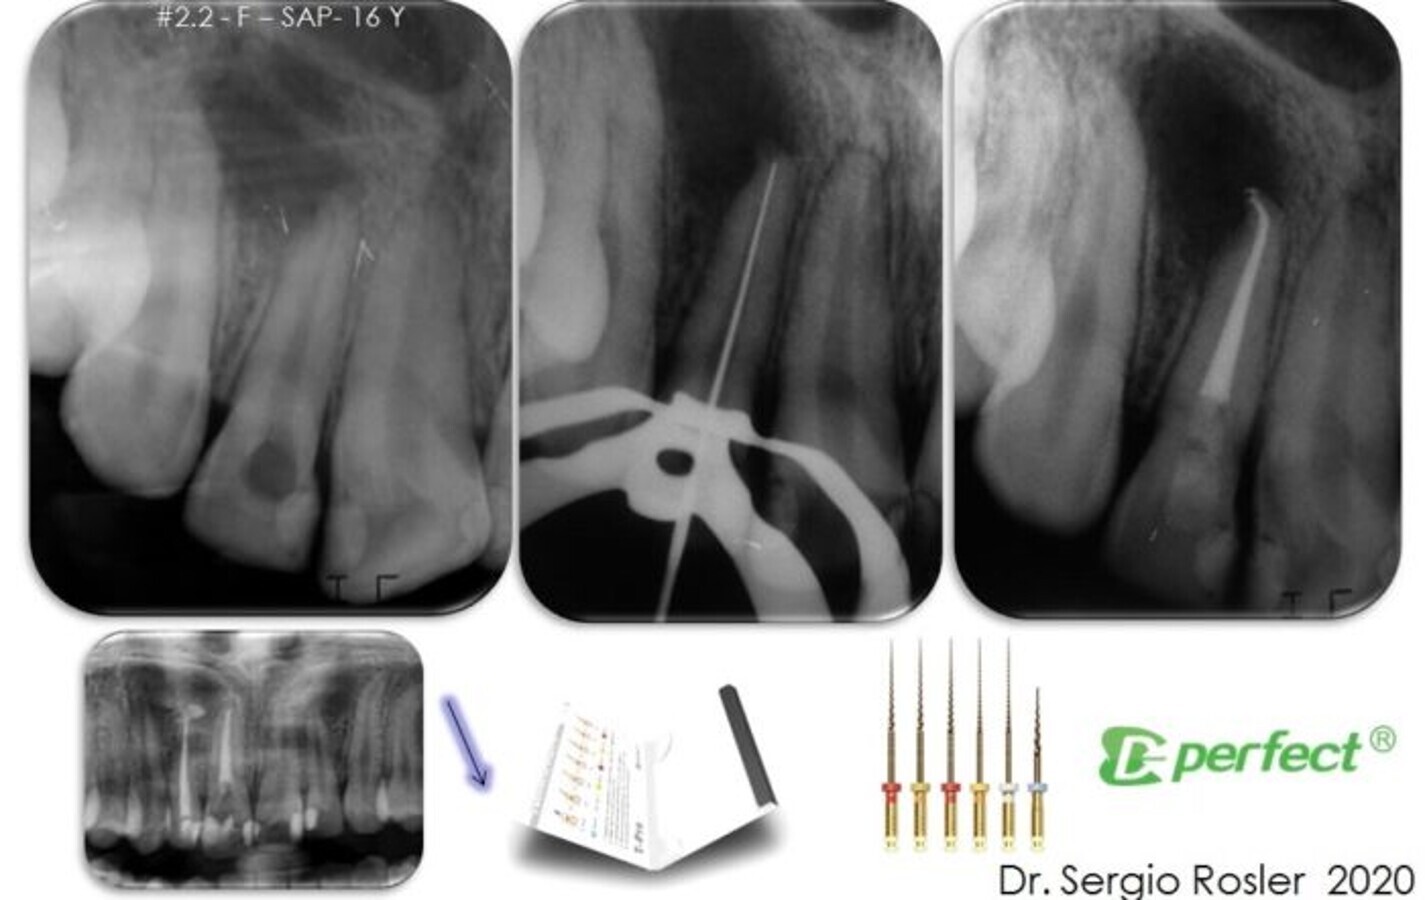

The maxillary lateral incisor apical curvature is respected after applying the shaping protocol with the T-Pro NiTi file system. (Image: Dr Sergio Rosler)